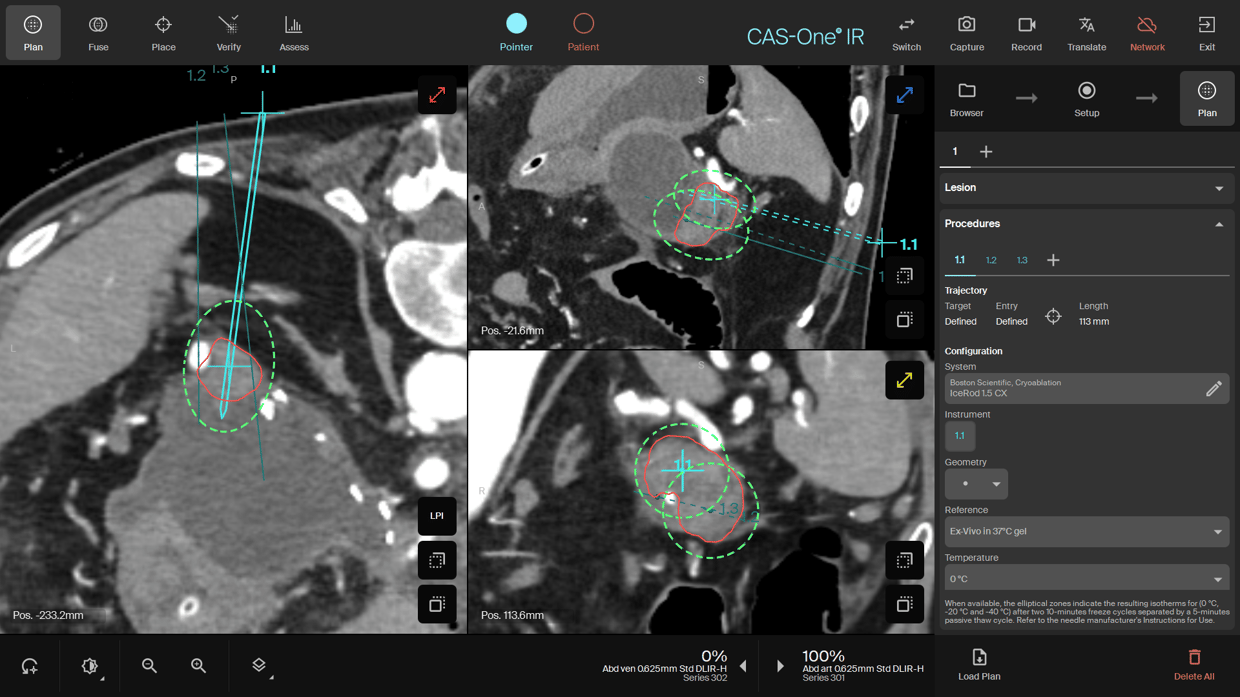

Planning scan (done at 0° to ensure no critical structures would be damaged) shows the planning of the two IceRod™ cryoprobes as well as the placement planning for the drainage catheter needle.

Planning of the cryo probes again at 0°C to assess the safety of the full Ice ball in relations to risky structures.